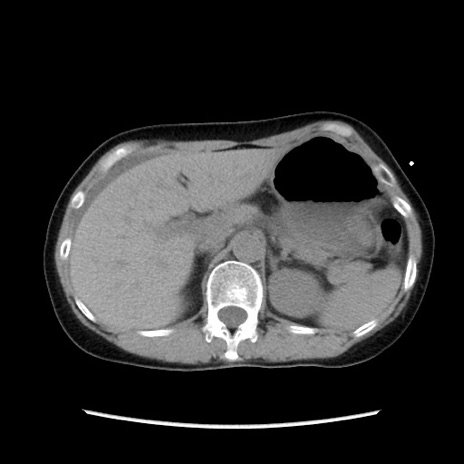

症例32(横断像)

【症例】40歳代 女性

【主訴】上腹部痛、嘔気・嘔吐

【現病歴】約9時間前頃から急に上腹部痛、嘔気、嘔吐が出現。改善しないため救急要請。

【既往歴】子宮頚癌(広汎子宮全摘術、放射線療法)、腸閉塞

【身体所見】腹部:平坦、軟、腸雑音亢進、上腹部を中心に腹部全体に圧痛あり。

【データ】WBC 8400、CRP 0.03